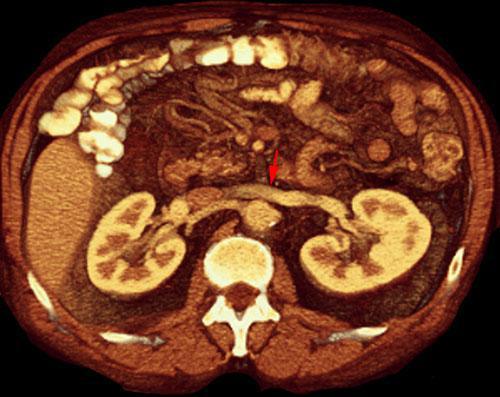

Vena renal izquierda circumaórtica

VR seccional. Visión axial caudal. TC contrastado en fase venosa mostrando la rama superior de la vena circumaórtica en la disposición habitual de la vena renal izquierda (flecha)